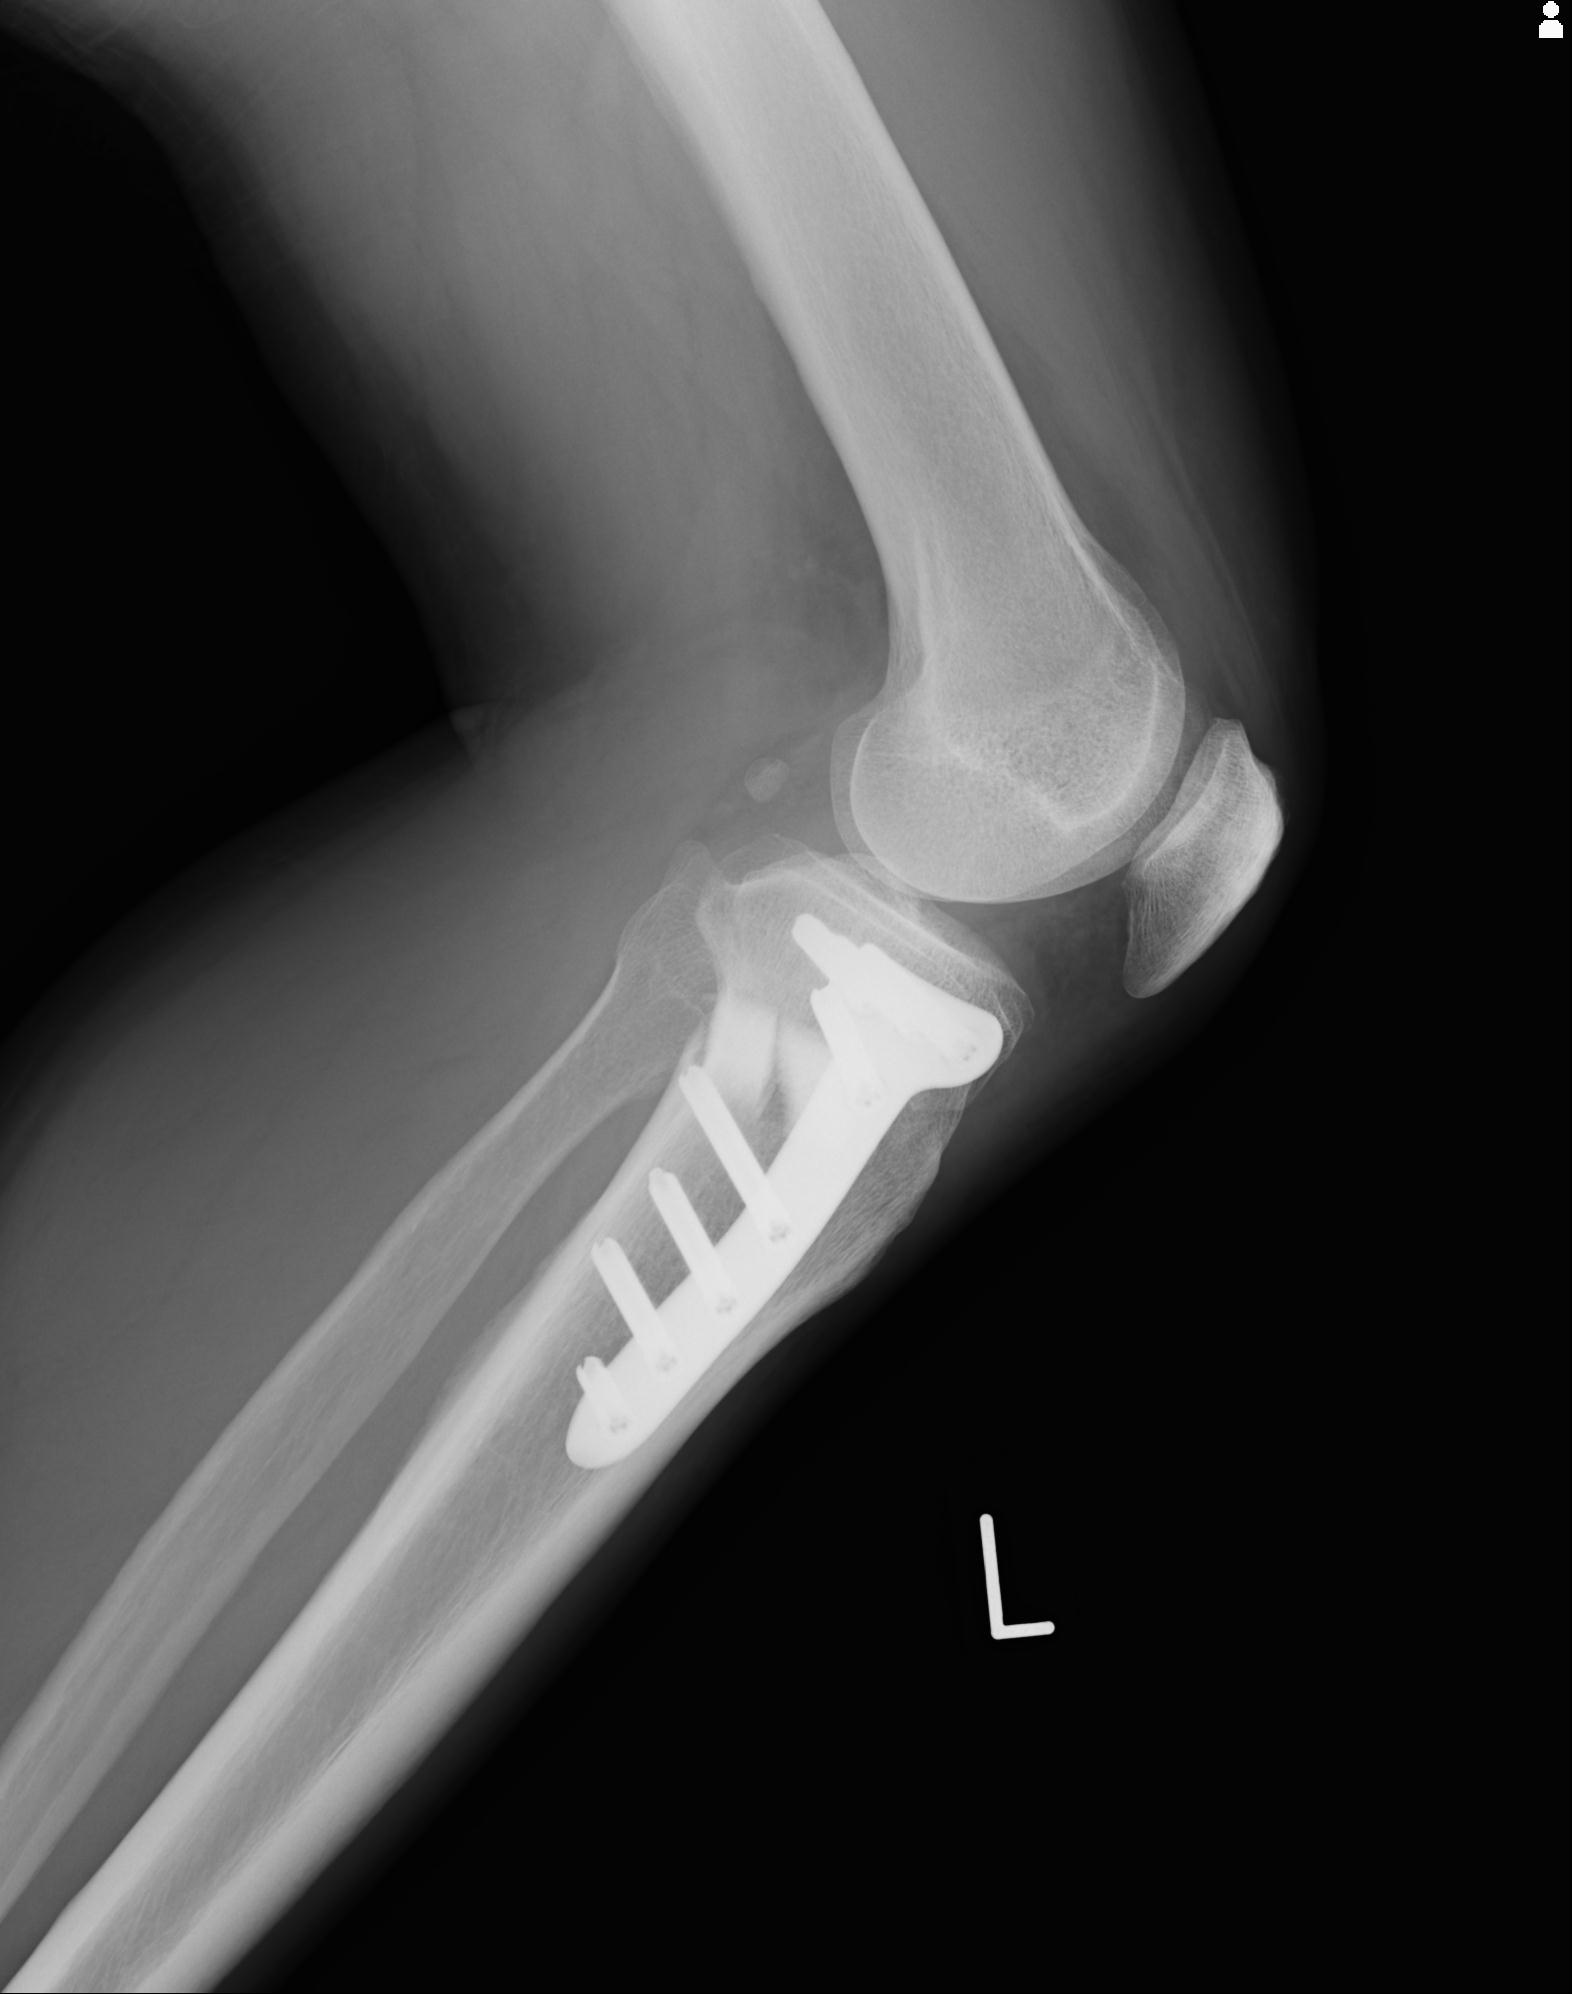

91983 11/16 左膝 2R 11/18 2R 55歳男性 脛骨骨切り術